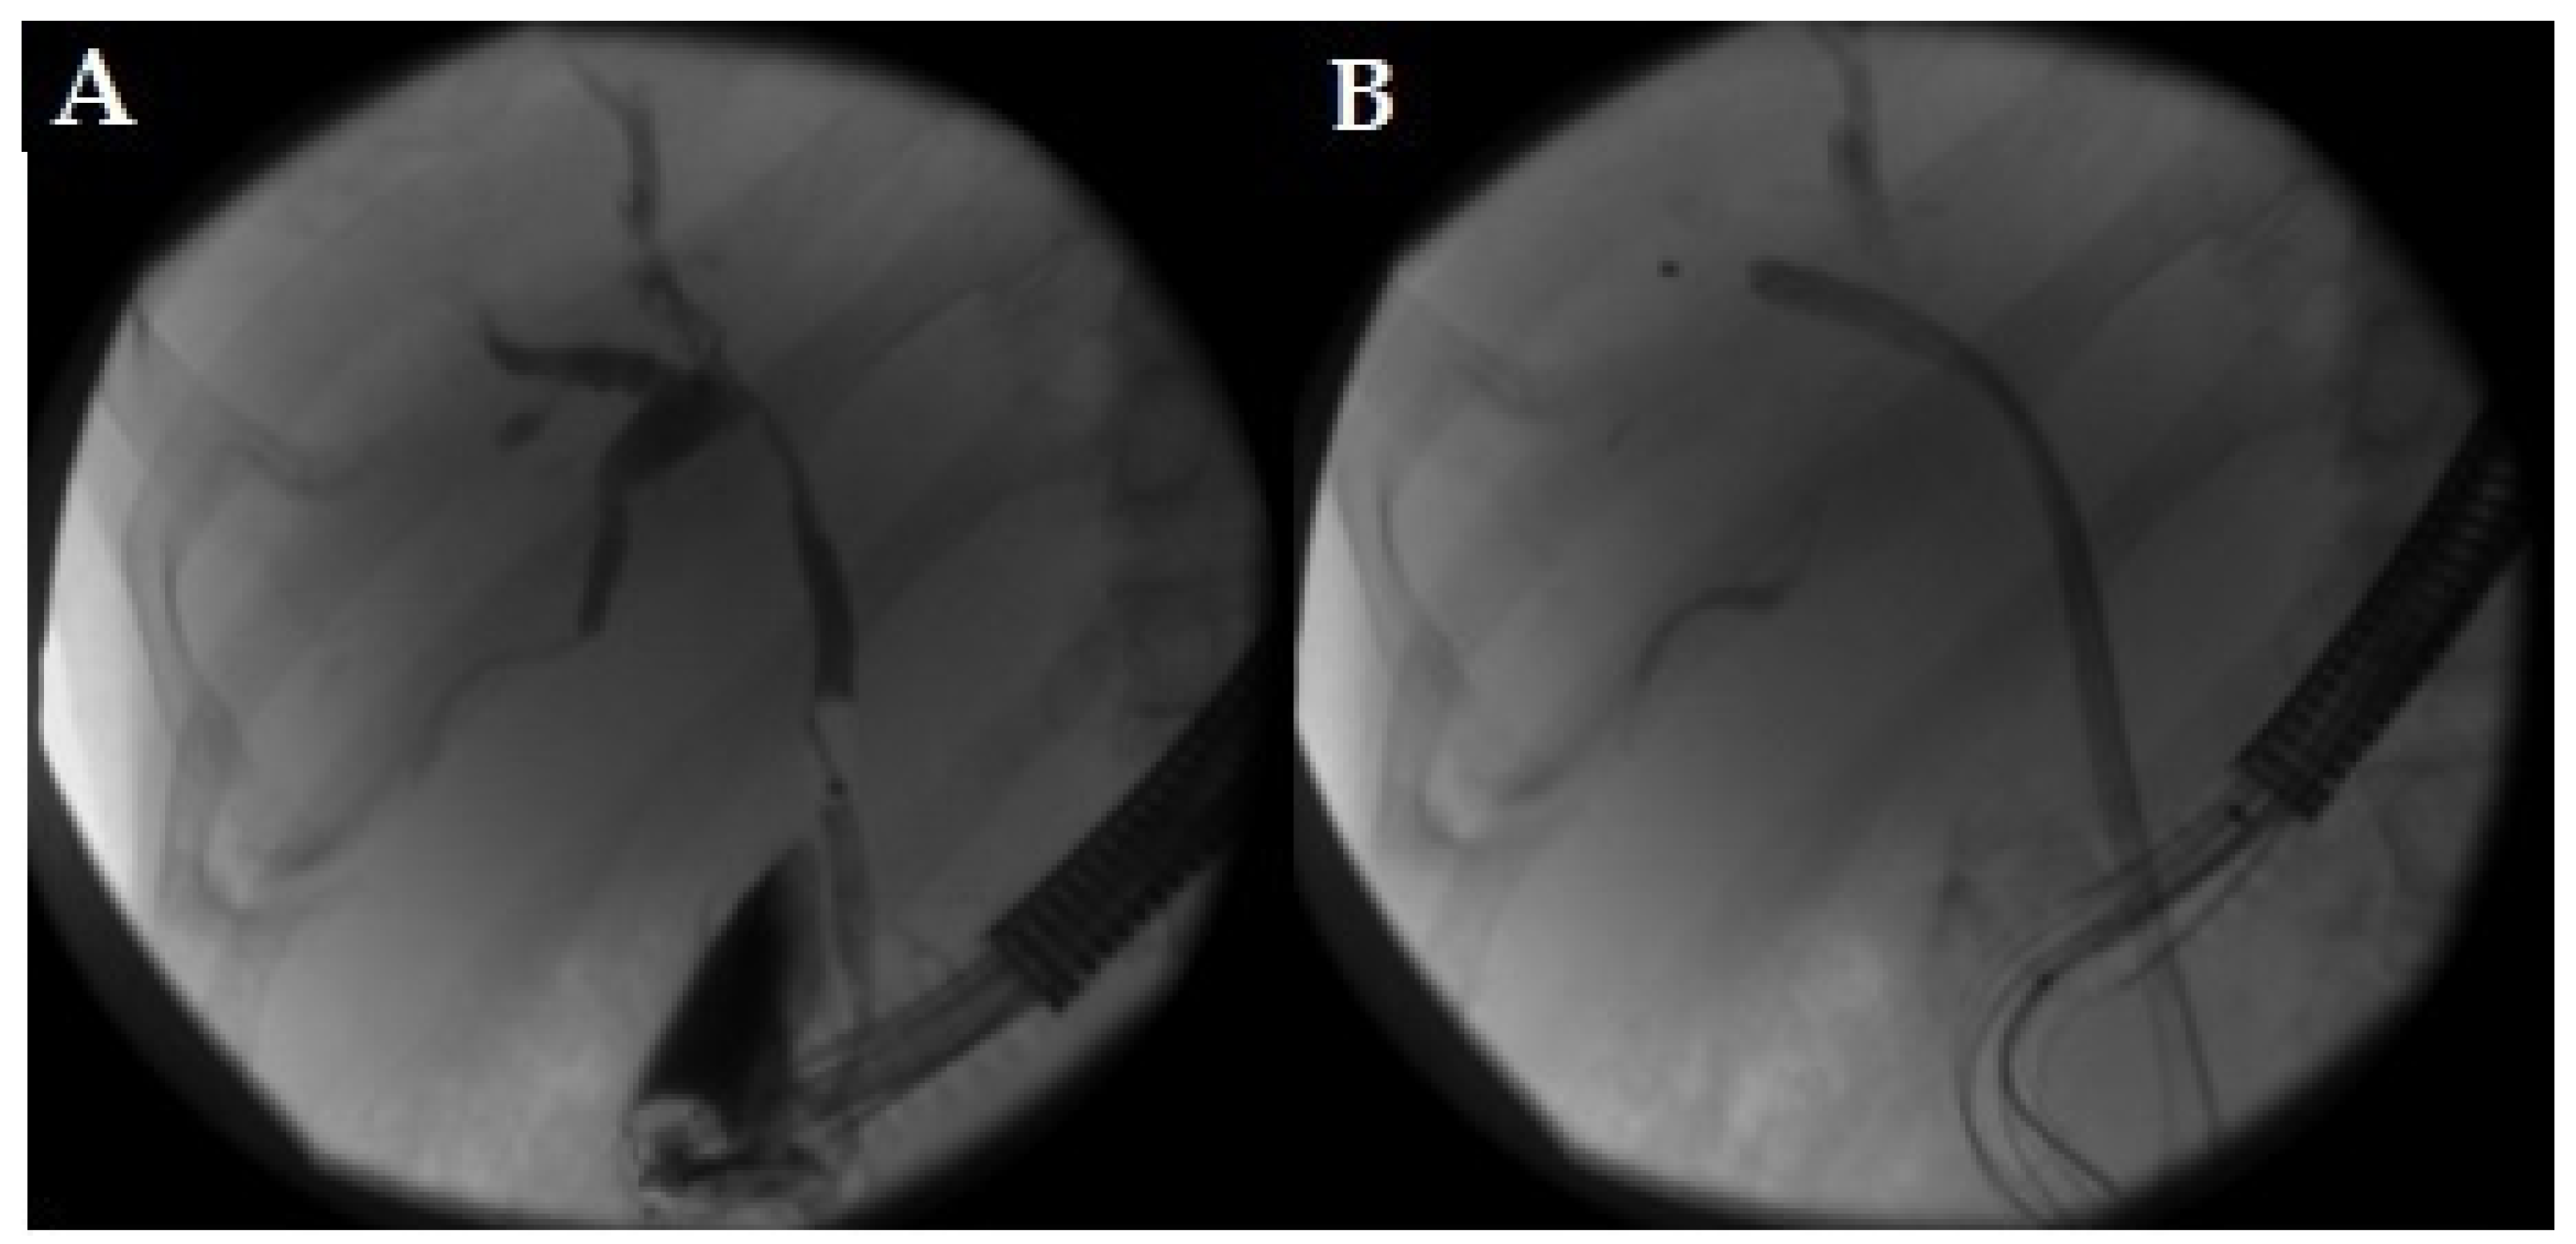

- Rivallin, P.; Lorenzo, D.; Hedjoudje, A.; Prat, F. Single-use duodenoscopes are an efficient tool for emergency ERCP in real life. Endosc. Int. Open 2022, 10, E1497–E1500. [Google Scholar] [CrossRef] [PubMed]